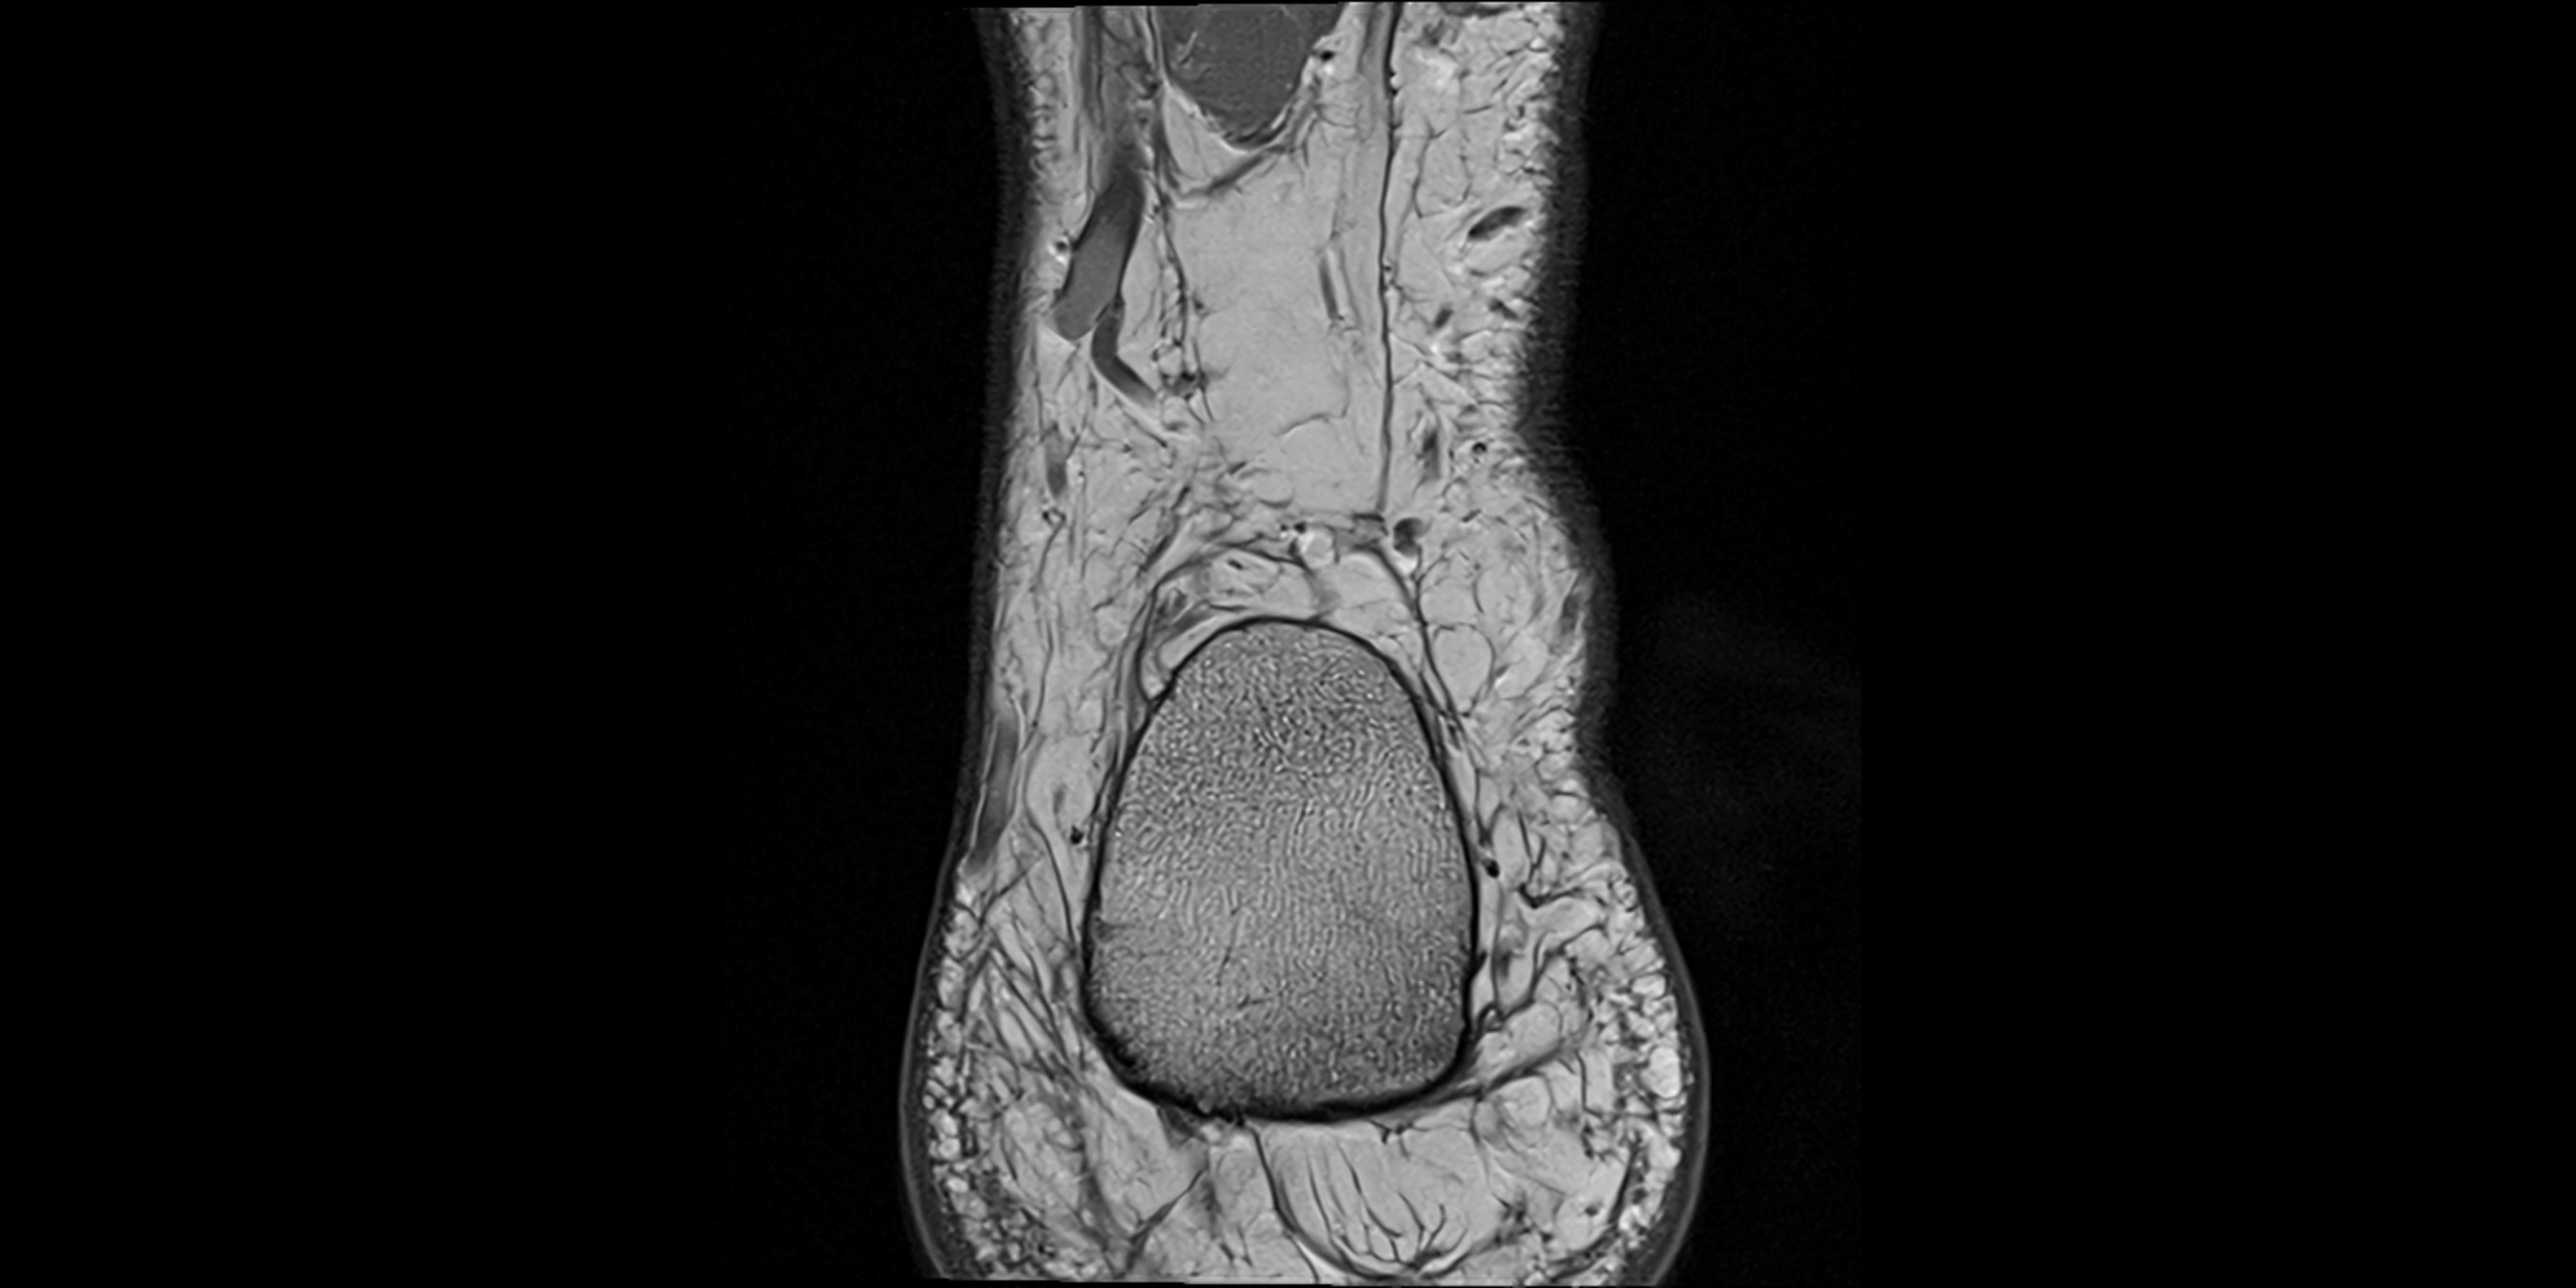

MRI image

image